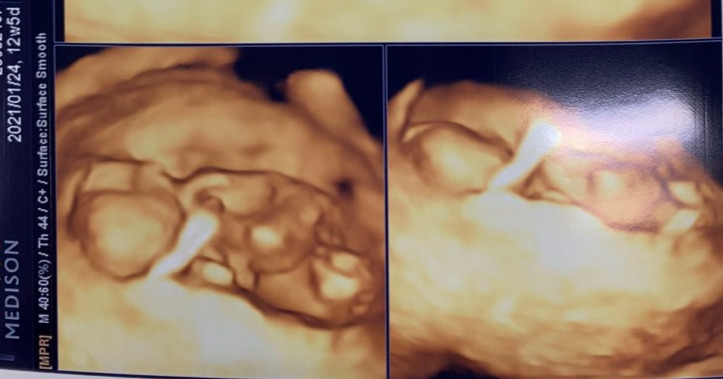

난 주 금요일 1차 정밀검사를 받았다. 10분가량 초음파를 했는데 이렇게 자세하게 행복이를 본 건 처음이었다. 정밀 초음파의 목적은 태아의 목둘레를 촬영하는 것이다. 목 뒤의 두께가 3mm를 넘으면 유전적 결함이 있을 수 있다고 한다. 감사하게도 행복이는 1.5mm로 정상범위에 있었다.

목둘레를 체크해야 하는데 행복이가 자꾸 몸을 꿈틀거리고 목을 잘 안보여줬다. 덕분에 더 오래 행복이를 볼 수 있었다. 녀석~ 행복이가 팔을 나의 배쪽으로 쭉 뻗는데, 그 모습이 너무 귀여웠다. 이런 작은 동작 하나가 사랑스럽고 감동인데, 이 마음을 잊지 말아야겠다고 생각했다.